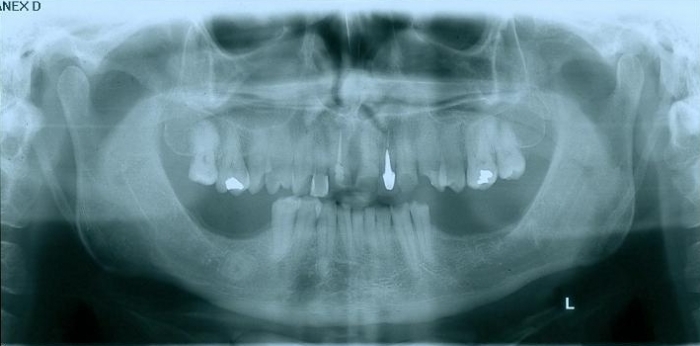

Raio - x inicial em 2014

Raio - x Próteses provisórias, em 2015

Próteses Provisórias, em 2015